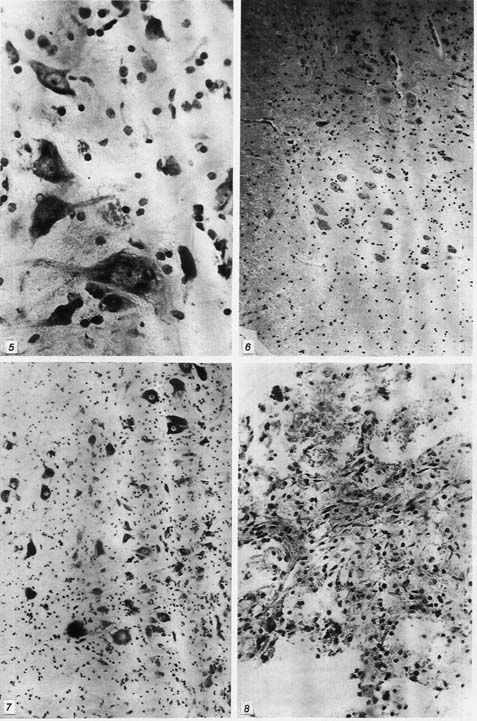

рис. 1-4

Рис. 1. Контузионный очаг спинного мозга с субарахноидаль-ным кровоизлиянием на 1-е сутки (контрольная серия). Окраска по Ван-Гизону. Ув. 70.

Рис. 2. Резко выраженный отек белого вещества спинного мозга с криброзностью тканей в параконтузионной зоне на 5-е сутки (контрольная серия). Окраска по Ван-Гизону. Ув. 140.

Рис. 3. Уменьшение отека белого и серого вещества спинного мозга на 14-е сутки (контрольная серия). Объяснение в тексте.

Рис. 4. Неполный хроматолиз в некоторых нервных клетках и клетки-тени на фоне умеренного отека вещества мозга на 14-е сутки (II серия). Окраска по Нисслю. Ув. 140.

В I (контрольной) серии эксперимента определяли травматические изменения спинного мозга в виде субдуральных и субарахноидальных и очаговых кровоизлияний в веществе мозга с асимметричными очагами конту-зионного некроза и некробиоза в задних столбах спинного мозга на фоне выраженного отека ткани мозга (рис. 1).

В параконтузионной зоне определяли венозную гиперемию, стазы, диапедезные кровоизлияния. Выражен отек вещества мозга с очаговой криброзностью ткани. В зоне контузии преобладают тяжелые необратимо измененные нервные клетки вплоть до вакуольной дистрофии и некроза отдельных клеток. Параконтузионная зона представлена различной степенью дистрофии нейронов в виде неравномерного тигролиза с отдельными клетками-тенями.

На 5-е сутки сохраняются расстройства кровообращения с нарастанием отека вещества мозга (рис. 2). Характер и степень выраженности повреждений клеток остаются прежними.

На 14-е сутки наблюдалось отграничение гематом грануляционной тканью с обильной макрофагальной реакцией. При этом отмечалось уменьшение отека белого и серого вещества спинного мозга, причем в зоне контузионного очага определялись тяжелые, а в периконтузионной зоне — различной степени дистрофии изменения нервных клеток (рис. 3).